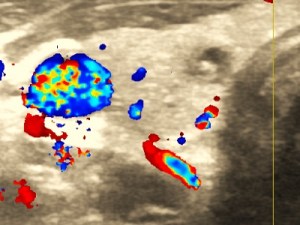

Węzły chłonne, guzki, przepukliny

Wykrywanie chorób powodujących powiększenie węzłów chłonnych. Guzki podskórne. Badanie zawartości przepuklin.

USG węzłów chłonnych-pozapalna limfadenopatia.